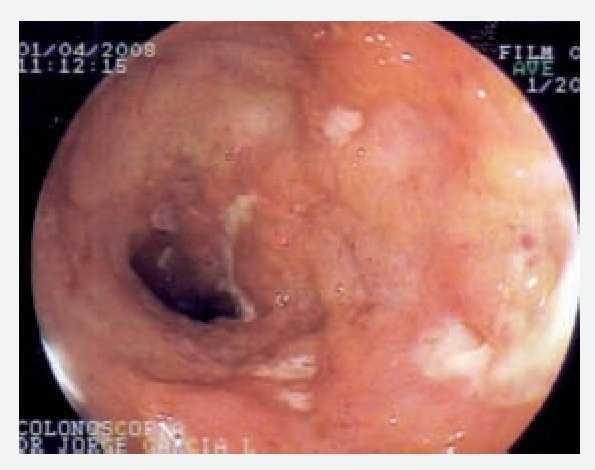

médico conservador. Acudió a consulta por presentar nuevamente dolor en mesogastrio intenso, de 8 horas de evolución, acompañado de vómito de contenido gastrobiliar y distensión abdominal importante. Se le realizó placa simple de abdomen la cual mostró niveles hidroaéreos con dilatación de asas de intestino delgado. Una vez resuelto el cuadro, se realizó tránsito intestinal que mostró dilatación de asas de intestino delgado con predominio de yeyuno (Figura 1). Se le practicó colonoscopia larga observando en íleon terminal, múltiples úlceras serpiginosas de 1 cm, presencia de edema y eritema periférico. La mucosa presentaba apariencia de empedrado alternada con mucosa de características normales (Figuras 2 y 3). Los cortes histológicos mostraron distorsión en la arquitectura a expensas de prolongaciones digitiformes de la lámina propia con inflamación, presencia de polimorfonucleares, eosinófilos y células plasmáticas con ausencia de granulomas, compatible con enfermedad de Crohn (Figura 4). El manejo terapéutico se baso la prescripción de azatioprina y mesalazina con buenos resultados sin presentar recidiva.

Figura 1. Estudio de contraste; tránsito intestinal que mostró dilatación de asas de intestino delgado con predominio de yeyuno